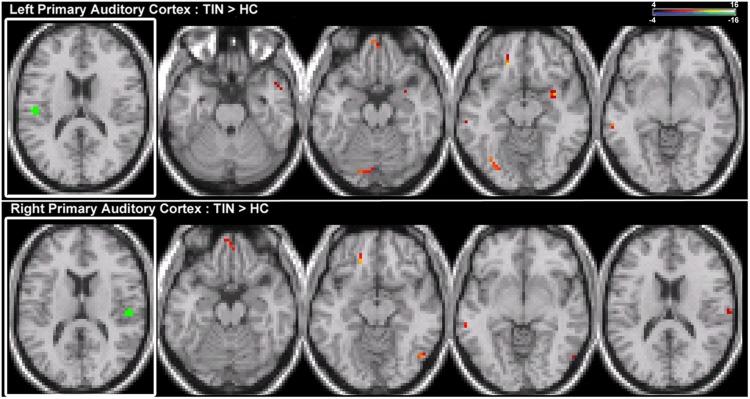

Tinnitus is a common auditory perceptual disorder whose neural substrates are under intense debate. One physiologically based model posits the dorsal striatum to play a key role in gating auditory phantoms to perceptual awareness. Here, we directly test this model along with the roles of auditory and auditory-limbic networks in tinnitus non-invasively by comparing resting-state fMRI functional connectivity patterns in chronic tinnitus patients against matched control subjects without hearing loss. We assess resting-state functional connectivity of the caudate dorsal striatum (area LC), caudate head (CH), nucleus accumbens (NA), and primary auditory cortex (A1) to determine patterns of abnormal connectivity. In chronic tinnitus, increases in ipsilateral striatal-auditory cortical connectivity are found consistently only in area LC. Other patterns of increased connectivity are as follows: (1) right striatal area LC, A1, CH, and NA with parietal cortex, (2) left and right CHs with dorsal pre-frontal cortex, (3) NA and A1 with cerebellum, hippocampus, visual and ventral pre-frontal cortex. Those findings provide further support for a striatal gating model of tinnitus, where dysfunctionally permissive area LC enables auditory phantoms to reach perceptual awareness.

耳鸣是一种常见的听觉感知障碍,其神经基础存在激烈争论。一种基于生理学的模型认为背侧纹状体在将听觉幻像门控至感知意识方面起关键作用。在此,我们通过比较慢性耳鸣患者与无听力损失的匹配对照受试者的静息态功能磁共振成像(fMRI)功能连接模式,直接非侵入性地测试该模型以及听觉和听觉 - 边缘网络在耳鸣中的作用。我们评估尾状核背侧纹状体(LC区)、尾状核头部(CH)、伏隔核(NA)和初级听觉皮层(A1)的静息态功能连接,以确定异常连接模式。在慢性耳鸣中,仅在LC区一致地发现同侧纹状体 - 听觉皮层连接增加。其他连接增加的模式如下:(1)右侧纹状体LC区、A1、CH和NA与顶叶皮层,(2)左右CH与背侧前额叶皮层,(3)NA和A1与小脑、海马体、视觉和腹侧前额叶皮层。这些发现为耳鸣的纹状体门控模型提供了进一步支持,其中功能失调的允许性LC区使听觉幻像能够达到感知意识。